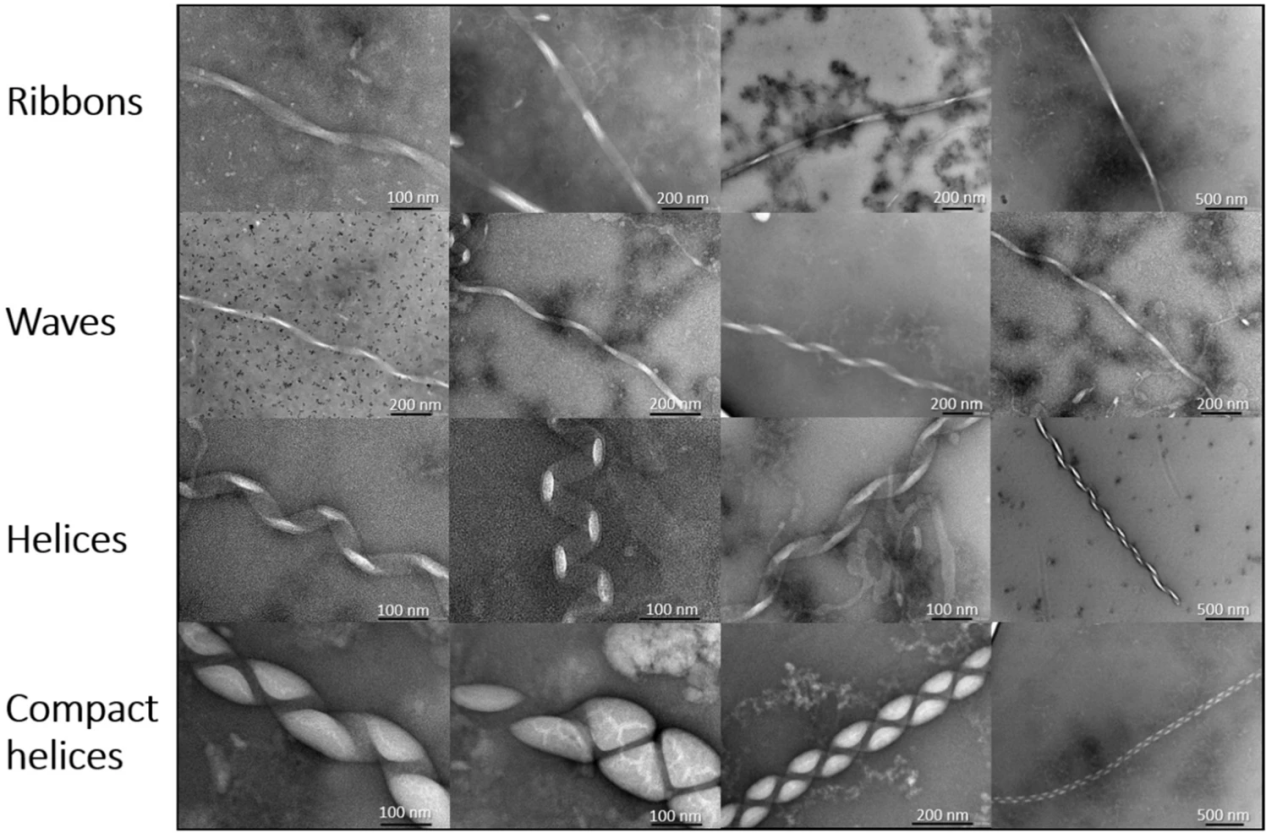

因此,乔迪·梅森教授和他的团队研究了在磷脂存在下αS如何错误折叠。结果他们发现了一系列以前从未发现过的错误折叠的蛋白质结构。这些错误折叠的αS纤维比以前报道的要大,并形状各异:有扁平带状、长长的波浪螺旋状、以及更紧凑更大的结构。

αS与DMPS脂质泡孵育后形成多种大型的原纤维晶型(这些结构是由100μMαS在30℃下200μM的DMPS脂质泡在190 h内聚集而成的)

研究人员使用透射电子显微镜(TEM)观察到了这些结构,并发现在脂质囊泡存在下,会形成的更大的宏装配体。此外,他们还发现,特定的膜相互作用在触发αS从可溶性形式转变为聚集形式方面发挥关键作用。